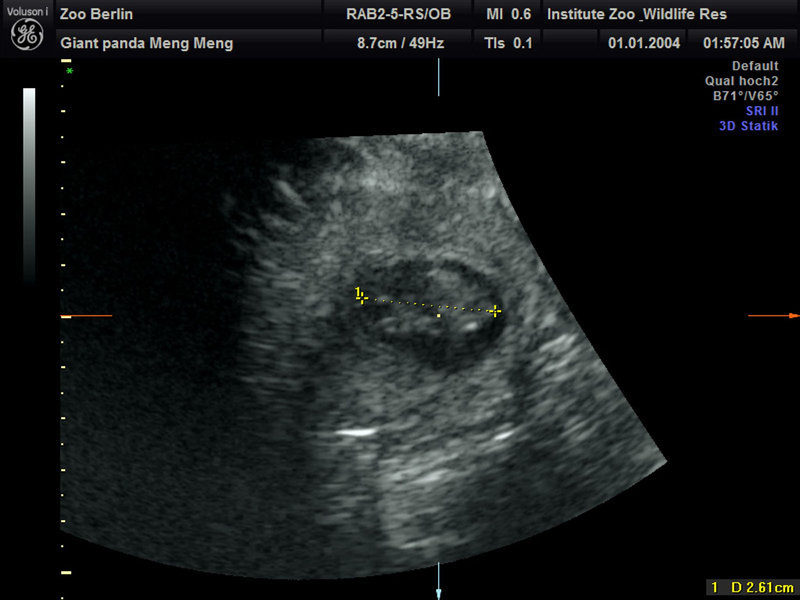

Berliner Zoo glücklich: Wieder Panda-Nachwuchs erwartet. ...

Wieder Panda-Nachwuchs im Berliner Zoo erwartet

Trächtig oder nicht? - Panda-Dame per Ultraschall untersucht. ...